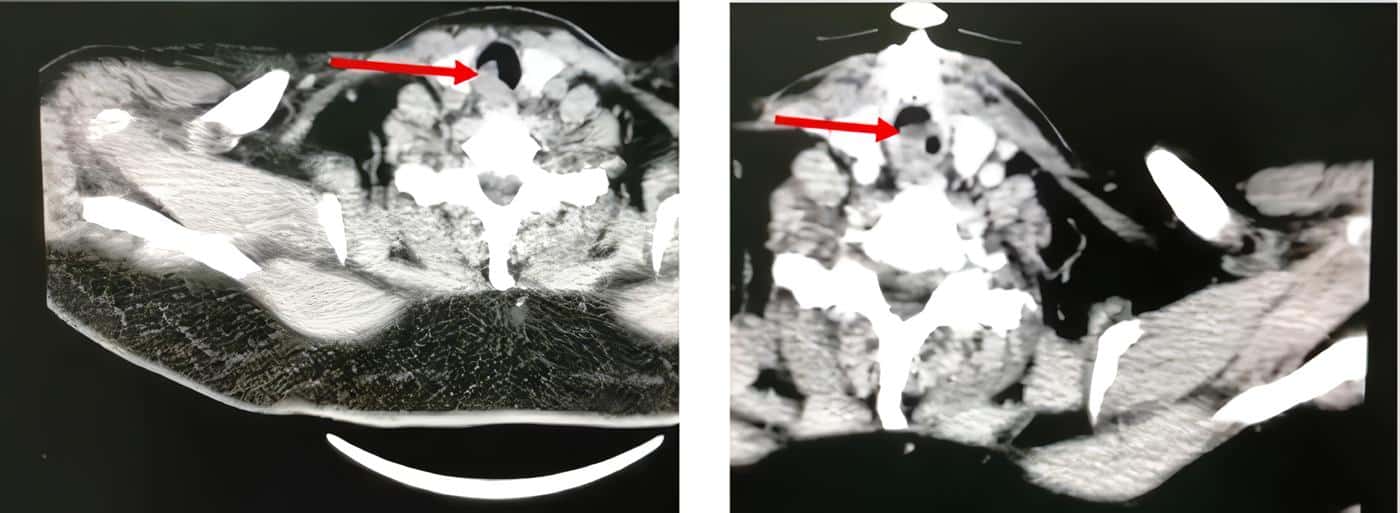

Paciente femenina de 66 años con cuadro clínico de tos persistente, acompañada de hemoptisis, a quien se le solicitó tomografía computarizada, la cual mostró una lesión que comprometía el 100 % de la circunferencia traqueal (Figura 1).

Figura 1. Tomografía axial computarizada de la paciente. Se evidencia lesión endoluminal (flecha roja) que compromete gran porcentaje de la circunferencia de la tráquea que explicaría la manifestaciones respiratoria de nuestro paciente. Fuente: Autores.